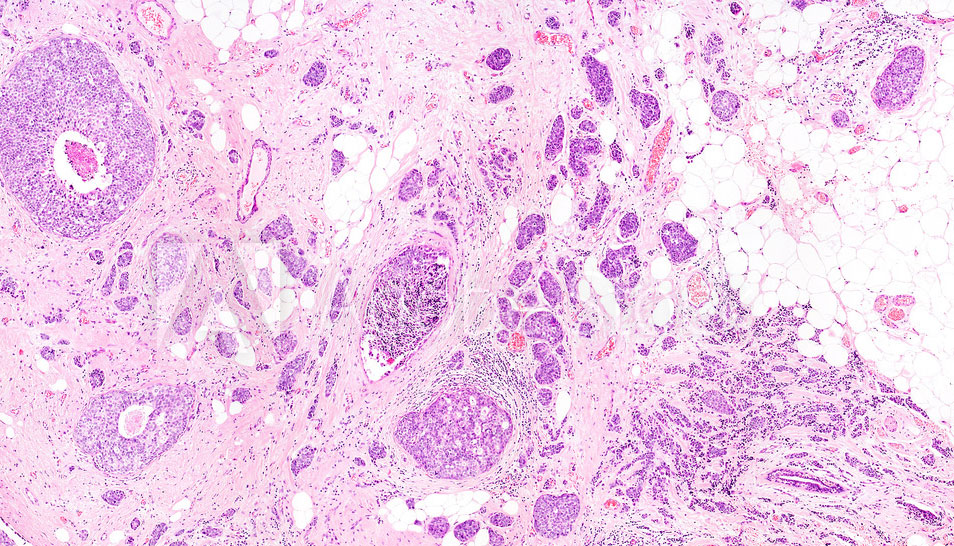

ESAME ISTOLOGICO MEDIANTE BIOPSIA CON AGO TRANCIANTE (CB - TRU-CUT)

Il prelievo per via percutanea di un frammento di tessuto mediante ago tranciante. Si esegue una anestesia superficiale e con assistenza ecografica si evidenzia la lesione. L’ago viene posizionato e si esegue il prelievo mediante un meccanismo a scatto che consente l’asportazione di un cilindro di tessuto della lunghezza di circa 1-2 cm. Successivamente si medica la piccola ferita chirurgica con steril strip e con una medicazione compressiva.La CB ha una sensibilità ed una specificità maggiori e permette la esecuzione di indagini biologiche (assetto dei recettori, indice di proliferazione cellulare) indispensabili nei casi in cui si debba effettuare una terapia medica preoperatoria neoadiuvante.